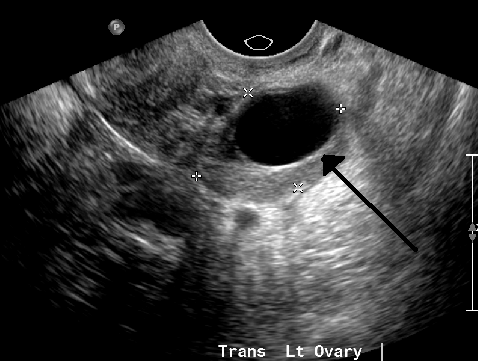

ultrasound: cyst

anechoic

ultrasound: articular cartilage

Anechoic (black) layer overlying the periosteum